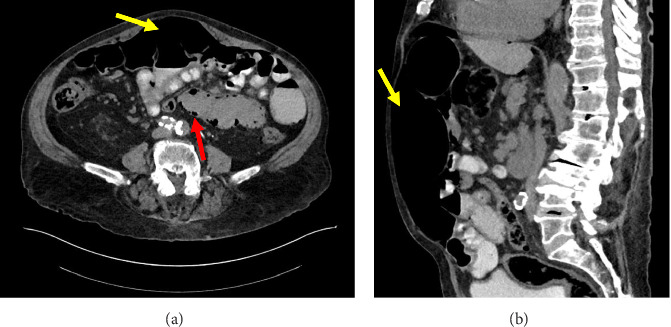

We present our experience with a patient with acute-on-chronic asymptomatic pneumoperitoneum with spontaneously resolving idiopathic pneumatosis intestinalis that was solely managed on close observation alone. This case is unique in that it details the approach to nonoperative management of massive free air under the diaphragm identified incidentally on routine preventative health screening and longitudinal follow-up over an 8-month period. In the absence of known and underlying systemic disease, efficient and coordinated clinical work-up and evaluation for comorbid diagnoses associated with pneumoperitoneum can serve to guide management and avoid unnecessary surgery for stable and asymptomatic patients.